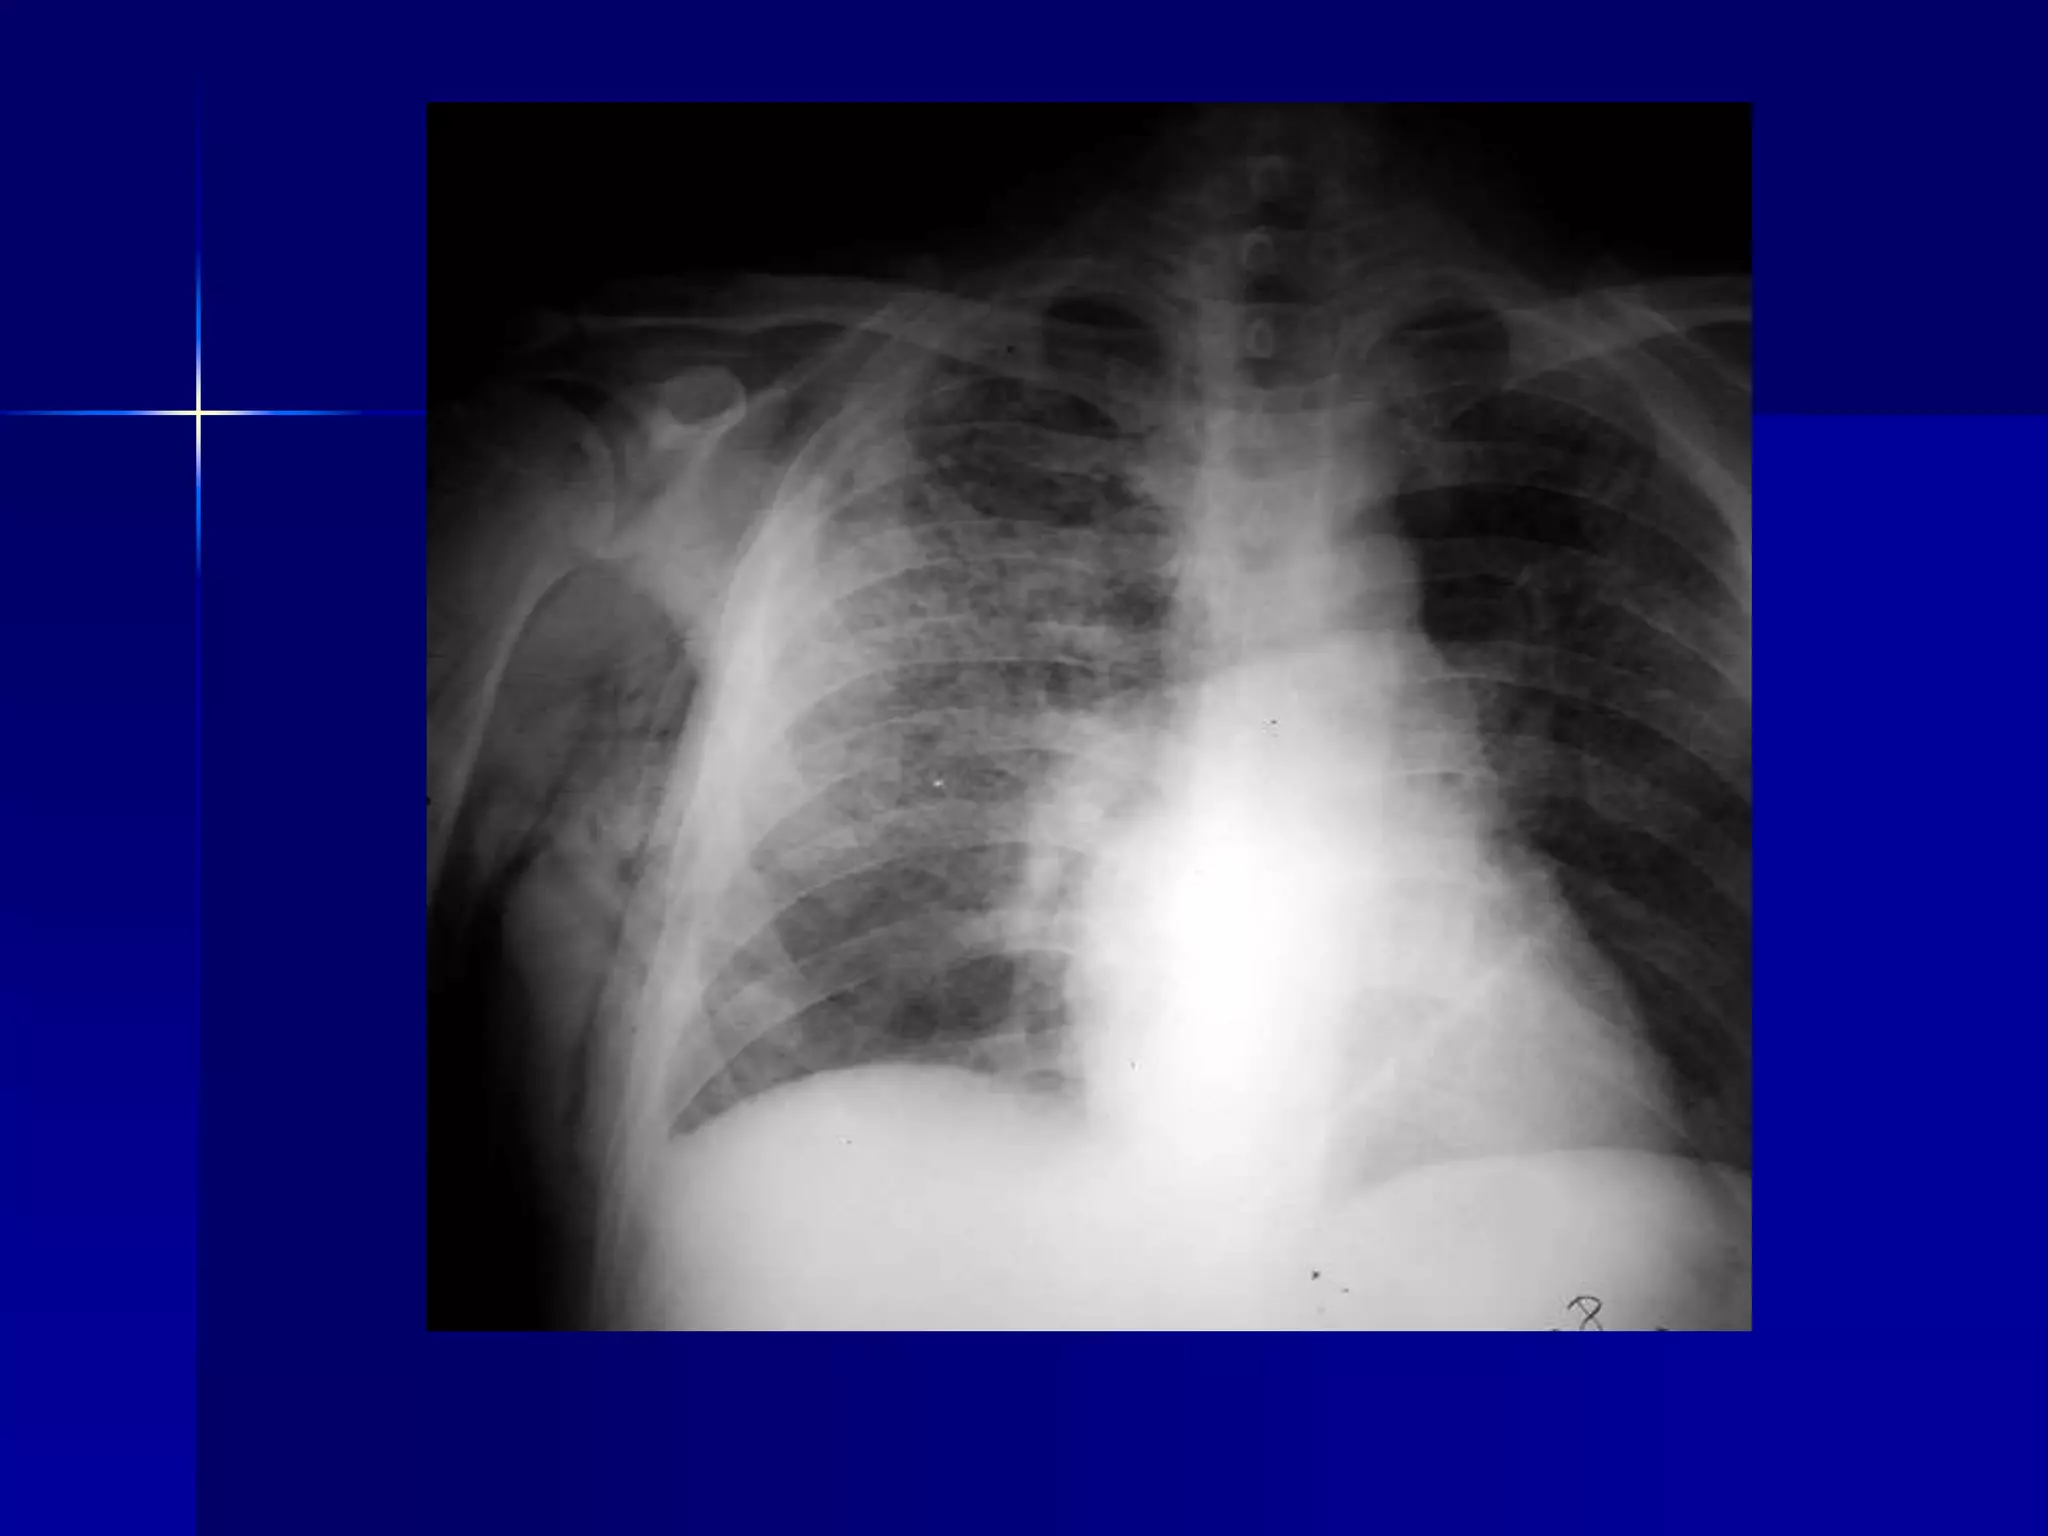

Atelectasis Right Lung

 Homogenous density right hemithorax

 Mediastinal shift to right

 Right heart and diaphragmatic

silhouette are not identifiable

 Atelectasis Right Lung

Atelectasis Right Lung  Homogenous density right hemithorax  Mediastinal shift to right  Right heart and diaphragmatic silhouette are not identifiable

 Atelectasis RightLung  Open Bronchus Sign  Homogenous density right hemithorax  Mediastinal shift to right  Right heart and diaphragmatic silhouette are not identifiable 